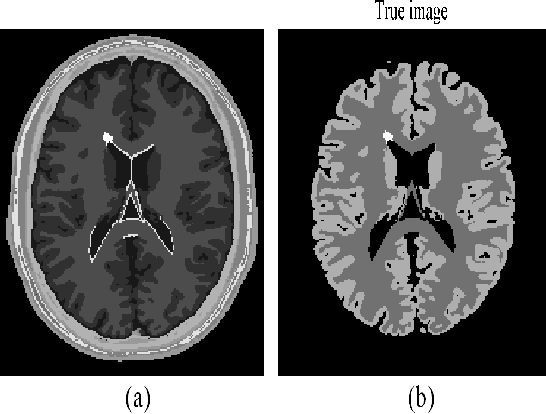

Abstract:Kernelized maximum-likelihood (ML) expectation maximization (EM) methods have recently gained prominence in PET image reconstruction, outperforming many previous state-of-the-art methods. But they are not immune to the problems of non-kernelized MLEM methods in potentially large reconstruction error and high sensitivity to iteration number. This paper demonstrates these problems by theoretical reasoning and experiment results, and provides a novel solution to solve these problems. The solution is a regularized kernelized MLEM with multiple kernel matrices and multiple kernel space regularizers that can be tailored for different applications. To reduce the reconstruction error and the sensitivity to iteration number, we present a general class of multi-kernel matrices and two regularizers consisting of kernel image dictionary and kernel image Laplacian quatradic, and use them to derive the single-kernel regularized EM and multi-kernel regularized EM algorithms for PET image reconstruction. These new algorithms are derived using the technical tools of multi-kernel combination in machine learning, image dictionary learning in sparse coding, and graph Laplcian quadratic in graph signal processing. Extensive tests and comparisons on the simulated and in vivo data are presented to validate and evaluate the new algorithms, and demonstrate their superior performance and advantages over the kernelized MLEM and other conventional methods.